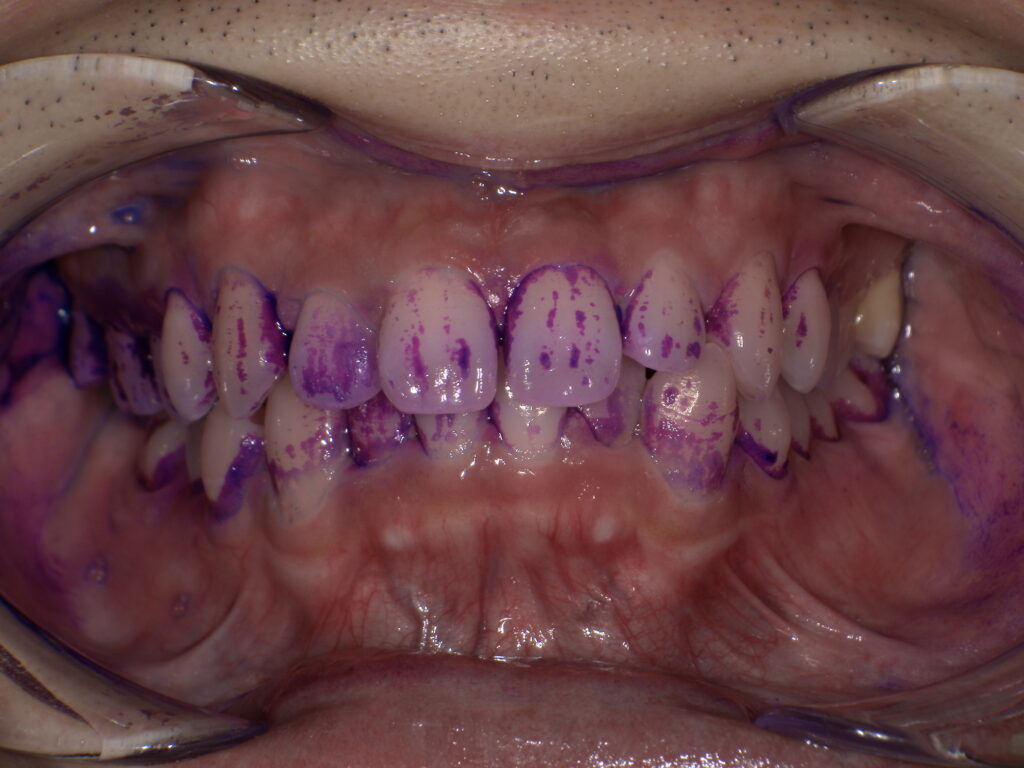

・染め出しとホームケアの確認

P①で最も重要なステップの一つです。歯周病治療の成功は、患者さんのご自宅での**ブラッシング(セルフケア)**にかかっていると言っても過言ではありません。染め出し液を使用し、磨き残しの部位を特定。患者さんの癖や歯並びに合わせた、効果的な歯ブラシの動かし方や、フロス・歯間ブラシの正しい使い方をマンツーマンで確認します。

↑きれいに見えていても、↓染め出しをするとこんなにも磨き残しがたくさんあります。

※患者様の許可を得て記載しております。